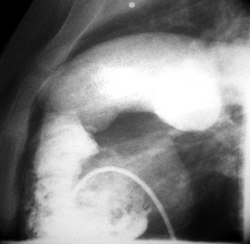

Καθετηριασμός καρδιάς: πιέσεις στην πνευμονική κυκλοφορία σχεδόν ίσες με της

συστηματικής (96% της συστηματικής), μειωμένο SpO2 του αρτηριακού αίματος (93%)

χωρίς διαφυγή αίματος από την αριστερή στη δεξιά κοιλία, υπερτροφία της δεξιάς

κοιλίας και διάταση του στελέχους της πνευμονικής και των κλάδων της (εικόνα

2).

Εικόνα 2. Καθετηριασμός καρδιάς

της ασθενούς. Υπερτροφία δεξιάς κοιλίας και διάταση του στελέχους της πνευμονικής

αρτηρίας και των κλάδων της.